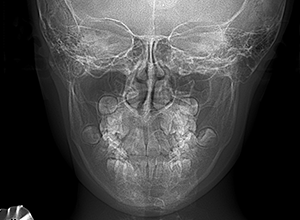

X-Ray

X-Ray所見

セファロ所見 下顎骨体部は大きく下顎枝は前傾しており下顎角は鈍角であった。上顎骨はやや劣位で奥行きがなく下顔面高は高くなっていた。

家族歴や側貌所見、下顎は大きいもののANBは2°でSellaに対して下顎頭は後方に位置していることなどから将来的に重度な下顎前突へ移行することは少ないと予測できた。

パノラマ所見 上顎アーチレングスディスクレパンシー(-)であるが、その他の異常所見は認められなかった。